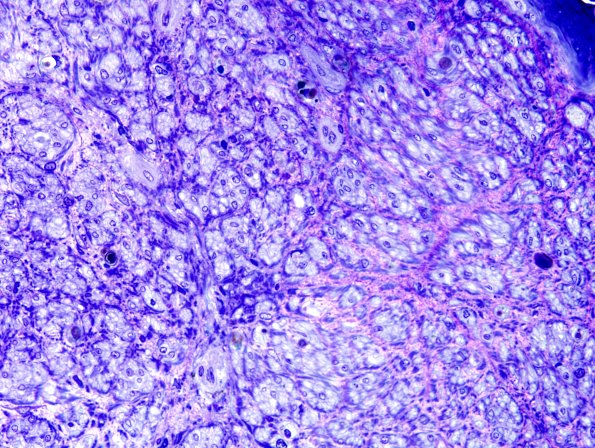

23D1 Vasculitis (Case 23D) Plastic 1

There is marked loss of small and large myelinated axons. (plastic section)